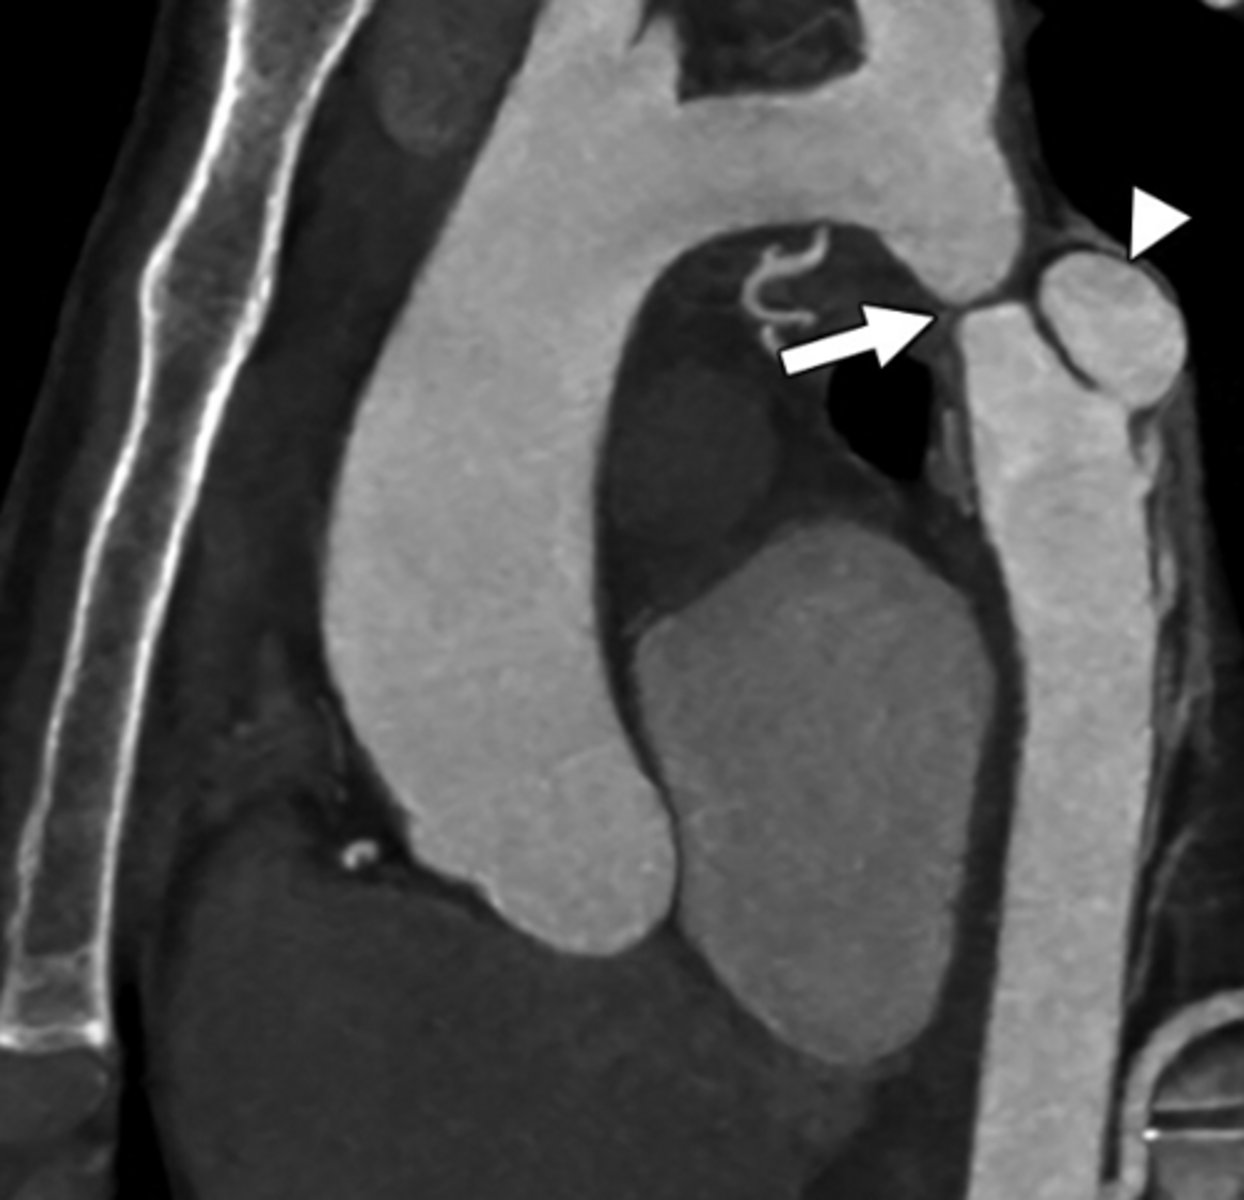

Dysphagia with aberrant vessel—most likely cause?

Aberrant right subclavian artery

What is a double aortic arch?

Persistence of both right and left aortic arches forming a vascular ring.